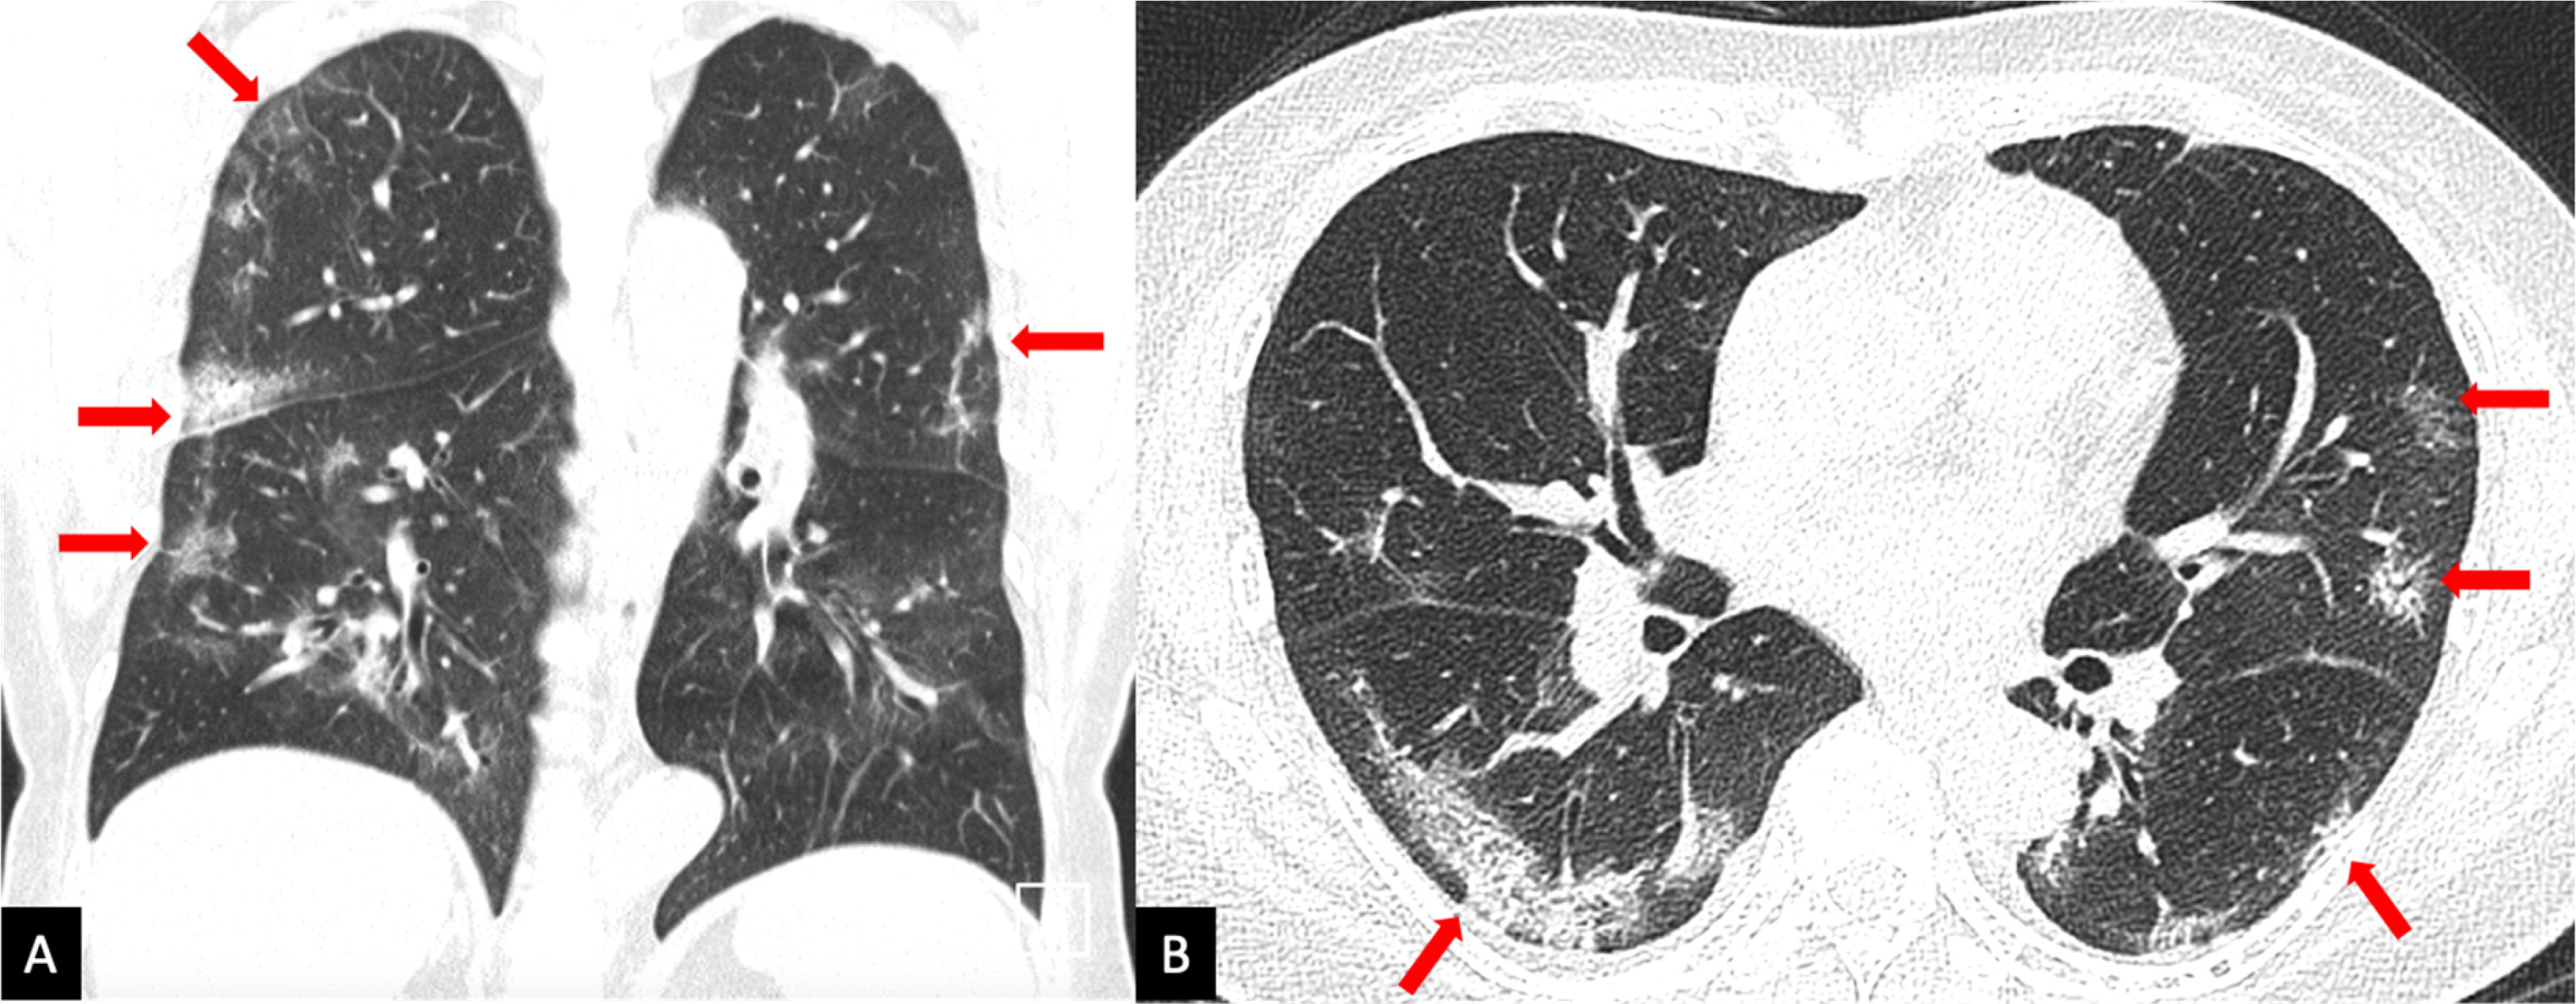

COVID-19 रोगियों के सीटी स्कैन से उनके फेफड़ों में सफेद धब्बों का स्पष्ट रूप से पता चला है - जिसे रेडियोलॉजिस्टों ने अपनी भाषा में ग्राउंड-ग्लास ओपेसिटी कहा है - क्योंकि वे स्कैन पर खिड़कियों के शीशों पर लगे धब्बों जैसे दिखाई देते हैं। पीड़ितों के फेफड़ों के सीटी स्कैन से ऐसे पैचेज़ नजर आए जो निमोनिया के होते हैं। लेकिन, कोरोना के मामले में ये ज्यादा ही गाढ़े हैं और फेफड़ों में हवा के जगह कुछ और ही भरा हुआ नजर आया।